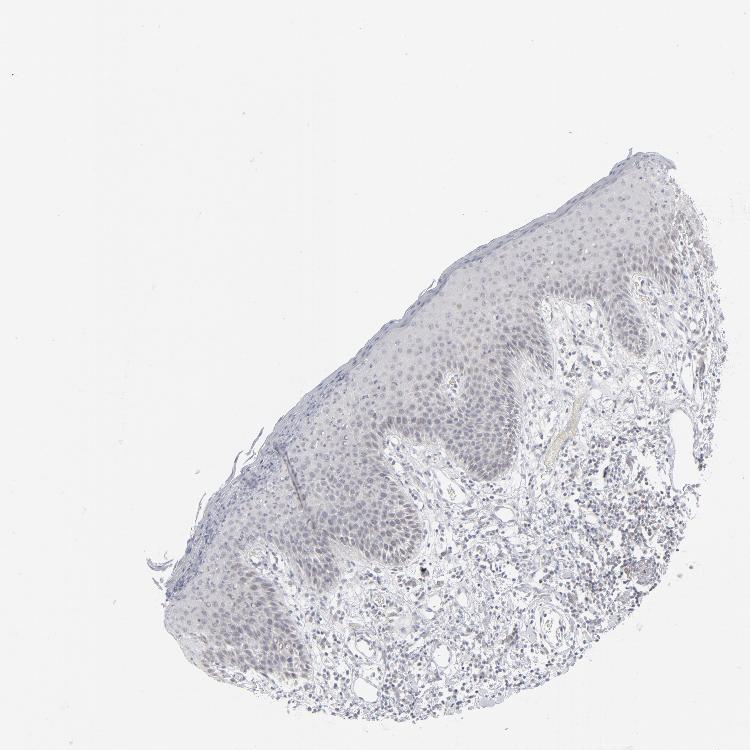

SKIN 1 - Antibody stainingi

Antibody staining in the annotated cell types in the current human tissue is reported as not detected, low, medium, or high, based on conventional immunohistochemistry profiling in selected tissues. This score is based on the combination of the staining intensity and fraction of stained cells.

Each image is clickable and will lead to virtual microscopy that enables deeper exploration of all samples and also displays staining intensity scores, fraction scores and subcellular localization as well as patient and tissue information for each sample.

Antibody HPA021816Antibody CAB002209

Langerhans MediumNot detected

Fibroblasts MediumNot detected

Keratinocytes MediumNot detected

Melanocytes MediumMedium